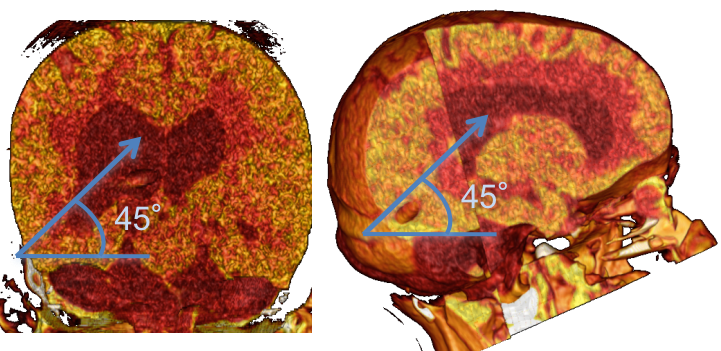

le cathéter est mis en place dans le carrefour en double obliquité, 45° en haut, en avant et en dedans, de façon à longer les parois de l’atrium

- abord rétro-auriculaire : à mi-chemin de la ligne conduit auditif externe-inion, un peu au-dessus (ce qui correspond à la suture lambdoïde)

- exposer correctement la dure-mère ; la perforer de façon à pouvoir mettre en place le cathéter en double obliquité sans être contraint par les limites du trou osseux (cf. ci-dessous).